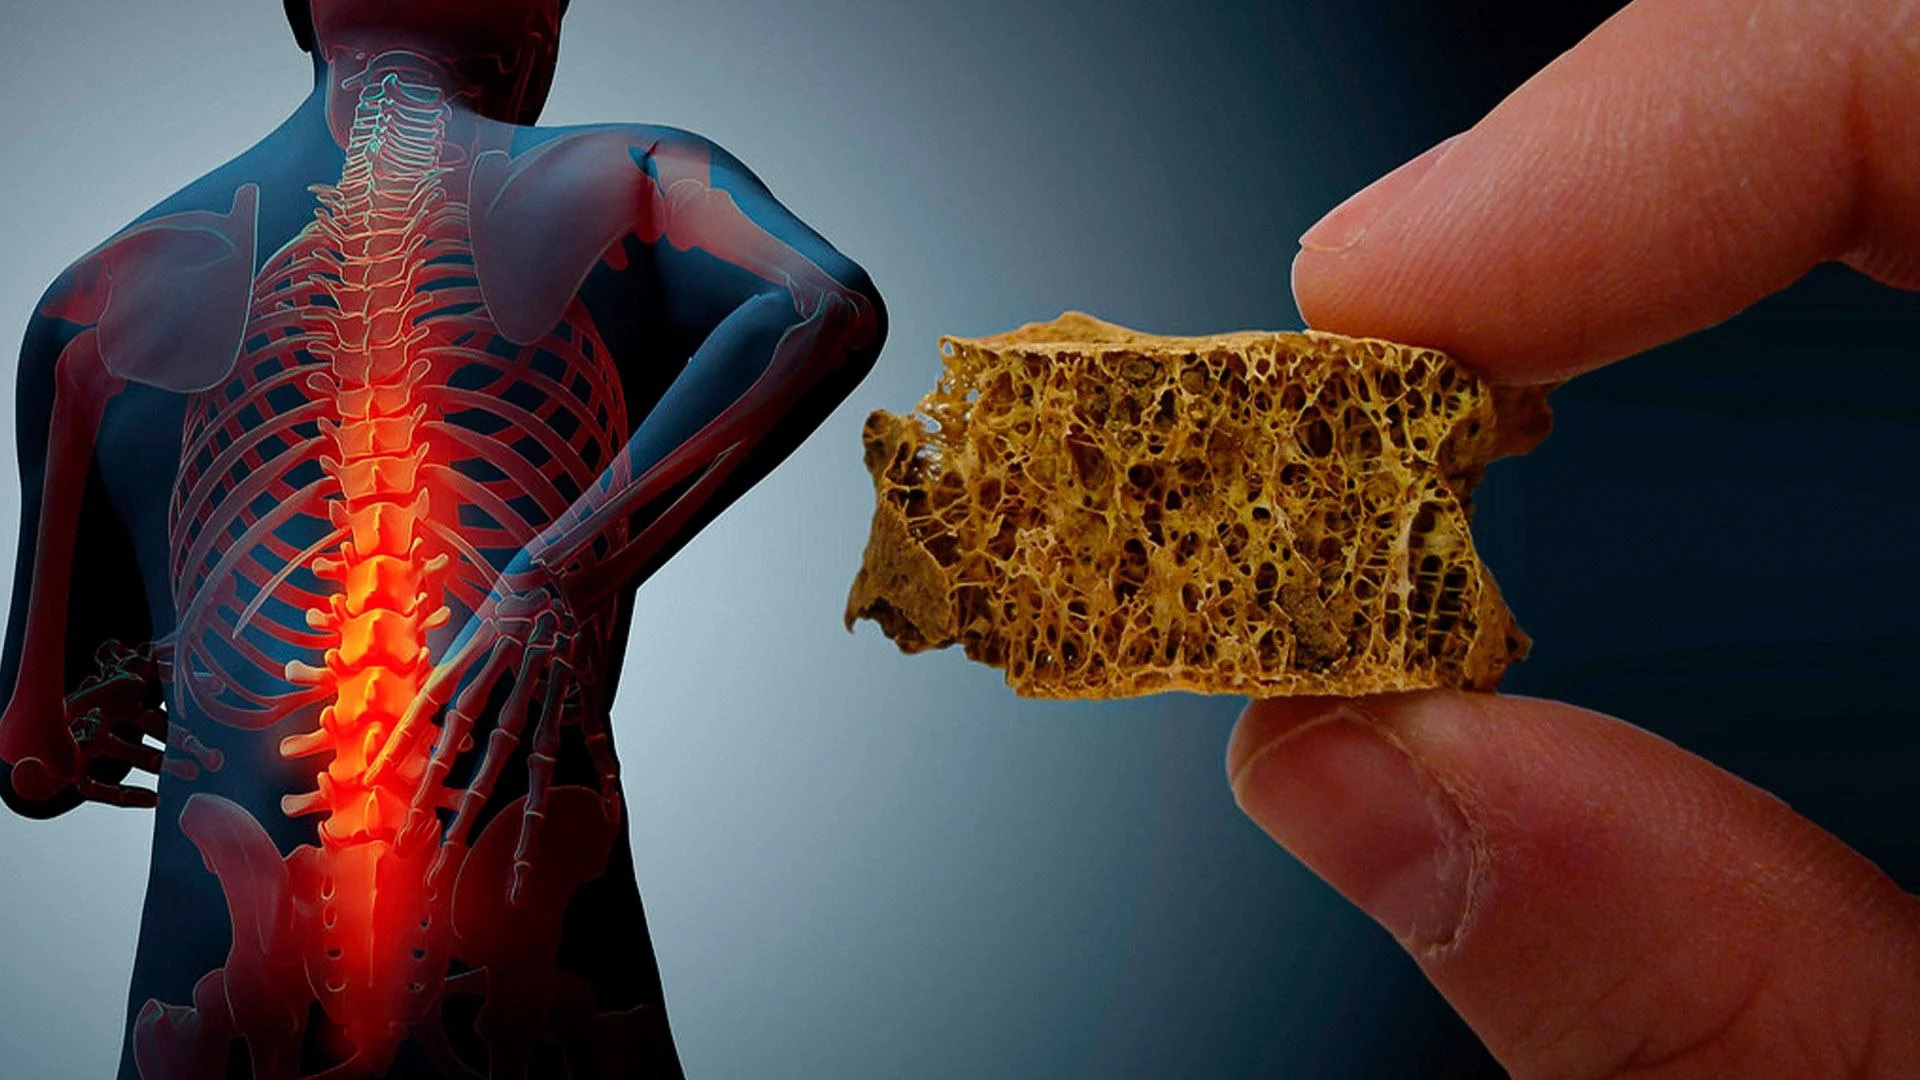

طبق تجربه، شکستگیهای مرتبط با استئوپروز اغلب در مچ دست، لگن و ستون فقرات رخ میدهند. همچنین این بیماری در زنان شایعتر است.

برای آنکه متوجه شویم پوکی استخوان چگونه اتفاق میافتد، باید فیزیولوژی استخوان را به صورت خلاصه بررسی میکنیم. استخوان یک بافت زنده و دائما در حال تغییر است که از یک لایه داخلی و یک لایه خارجی تشکیل میشود. لایه خارجی نازک و متراکم است و لایه داخلی دارای ساختار خانه-خانه و مشابه کندوی زنبور عسل است. بافت استخوان از فیبرهای پروتئینی مستحکم و با خاصیت الاستیکی به نام کلاژن، فسفات کلسیم و مواد معدنی دیگر تشکیل میشود. ترکیب شبکه کلاژن و فسفات کلسیم باعث استحکام و در عین حال انعطافپذیری در برابر ضربات میشود.

زمانی که حفرههای میان شبکهها در لایه داخلی، به علت تحلیل کلسیم بزرگ میشوند، استخوان به تدریج خالی شده و پوکی استخوان اتفاق میافتد. بنابراین استخوان شما ضعیف شده و با کوچکترین ضربهای دچار شکستگی میشود. از دست رفتن تراکم استخوانها به طور خاموش و بی سروصدا اتفاق میافتد و اغلب مواقع نیز هیچ علامتی تا زمان شکستگی ندارد.